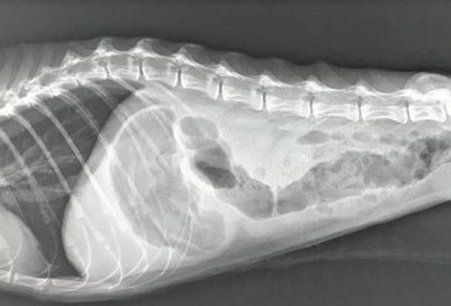

急性胃腸炎になった猫のレントゲン写真。急性胃腸炎になると細菌の発生や腸管の運動が悪くなることでガスが発生。それにより苦しくなって嘔吐をしたり、消化不良で下痢をしたりします